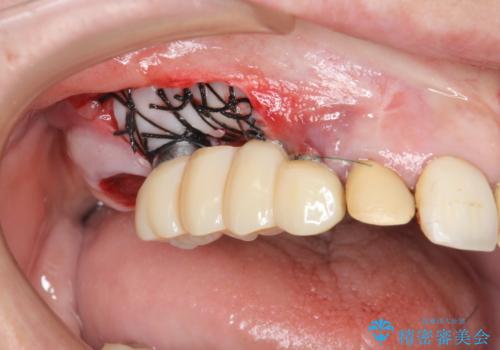

- 他院で1本インプラントを入れたまま治療に通うことができなくなり、途中からの治療を希望され来院されました。

既に埋入されているインプラントは位置が悪いのでそのまま骨内に留置することとし、新たに咬合機能を回復すべく3本のインプラントを埋入すると同時に吸収した骨幅を増やし、安定してインプラントで噛める環境整備を目指します。

- 120万円(インプラント×3 チタンカスタムアバットメント×3 メタルボンドクラウン×3 骨造成 歯肉移植)費用は治療当時の料金となります

インプラントが長持ちするために、インプラント周囲の十分な骨量・角化歯肉の存在・安定した咬合を一つづつ整備する治療を行いました。